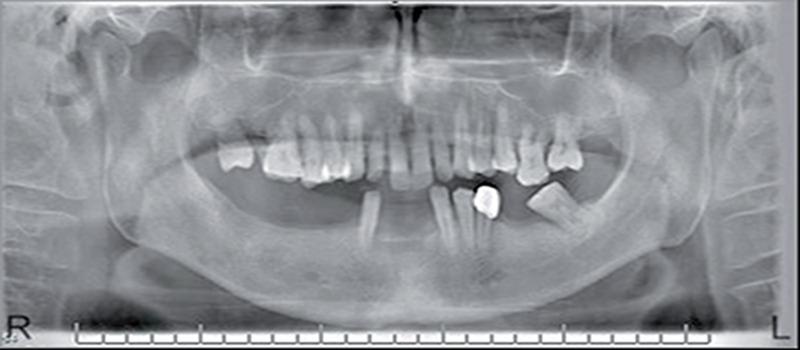

An arteriovenous malformation (AVM) is composed of abnormal communications between arteries and veins without the normal intervening capillary bed. AVM of the head and neck is a rare vascular anomaly. We present here an unusual case of AVM with the size of 4x3 cm at the left posterior palatal area. Incisionel biopsy revealed AVM. Resection of the lesion following angiography was suggested to the patient however, he refused the treatment. The patient was considered to be under control. AVM should always be kept in mind in the differential diagnosis of palatal swellings.

动静脉畸形(AVM)由动脉与静脉之间的异常交通组成,其间无正常的毛细血管床。头颈部动静脉畸形是一种罕见的血管异常。我们在此呈现一例不寻常的动静脉畸形病例,位于左侧腭后区域,大小为4×3厘米。切开活检显示为动静脉畸形。血管造影后建议患者切除病变,然而,他拒绝了治疗。该患者被认为病情得到控制。在腭部肿胀的鉴别诊断中应始终考虑到动静脉畸形。